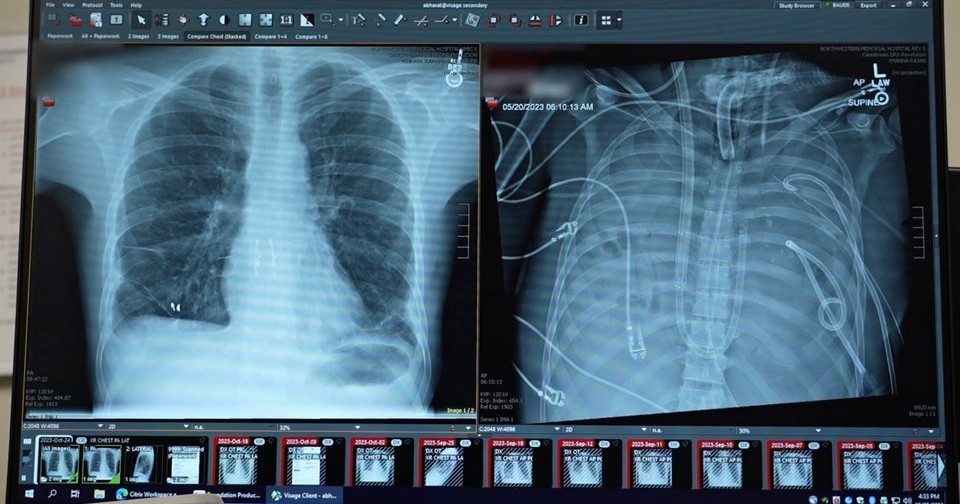

Шанс испытать систему представился, когда в университетскую клинику поступил ранее здоровый 33-летний мужчина, у которого на фоне гриппа В развился ОРДС. В последующие шесть недель у него развилась быстро прогрессирующая некротизирующая пневмония, вызванная карбапенем-резистентной синегнойной палочкой (Pseudomonas aeruginosa), с двусторонними эмпиемами (скоплениями гноя в плевральной полости), требующими постоянного дренирования. Несмотря на антибактериальную терапию широкого спектра и полную венозно-артериальную ЭКМО у пациента периодически наступали перерывы в сердечной деятельности, свидетельствующие о рефрактерном септическом шоке. В силу этого врачи приняли решение удалить оба легких с обширной хирургической очисткой плевральных полостей, чтобы устранить источник инфекции и создать условия для возможной трансплантации.

После операции пациента подключили к искусственному легкому. Уже через несколько часов появились выраженные улучшения гемодинамики. Потребность в вазопрессорных препаратах (норадреналине и вазопрессине) быстро уменьшалась и отпала через 12 часов после вмешательства. Центральное венозное давление во время нахождения на аппарате составляло 8–15 миллиметров ртутного столба, то есть застоя крови не было. Сывороточный уровень лактата, перед пневмонэктомией достигавший 8,2 (при норме 0,5–2,2) миллимоль на литр, через 12 часов снизился до 1,8, а через 24 часа — до 1,0 миллимоль на литр. Перфузия почек была нормальной (отхождение мочи 1,0–1,5 миллилитра на килограмм массы тела в час при нормальном уровне креатинина в крови). Уровни печеночных ферментов и билирубина были в норме. Насыщение крови кислородом превышало 92 процента, другие показатели газового состава крови были нормальными. ЭхоКГ каждые 12 часов показывало нормальный сердечный кровоток без перегрузок отделов сердца, внутрисердечных тромбов не было без назначения антикоагулянтов.

Через 48 часов нахождения на искусственном легком пациенту выполнили двустороннюю трансплантацию донорских легких по стандартной технологии. Вирус гриппа В и синегнойная палочка у него определялись во время операции, но не после нее. Через три дня пациента отключили от ЭКМО, через неделю — от искусственной вентиляции и через восемь недель выписали из стационара. Чрезбронхиальные биопсии через 3, 6, 9 и 12 месяцев не выявили признаков острого отторжения, через 24 месяца трансплантат функционировал полноценно, функция внешнего дыхания была удовлетворительной, уплотнений и выпота на рентгенограмме грудной клетки не было. Патологоанатомическое исследование удаленных легких выявило обширный некроз и фиброз с диффузной инфильтрацией иммунными клетками и отложениями коллагена. Секвенирование РНК одиночных клеток и пространственный транскриптомный анализ подтвердили необратимые диффузные повреждения легких с тяжелым фиброзом.